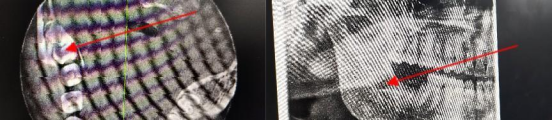

现代根管治疗术